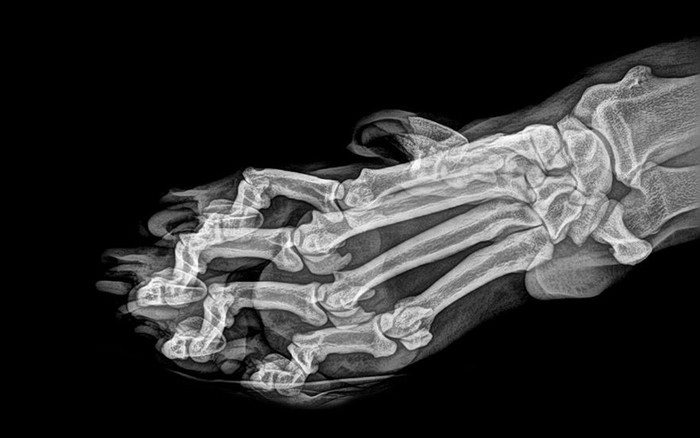

Jakarta - Kebun binatang London dan Oregon merilis foto X-Ray sejumlah hewan-hewannya. Foto tersebut kerap digunakan untuk memantau kondisi kesehatan para hewan.

Deretan Foto X-Ray Para Hewan